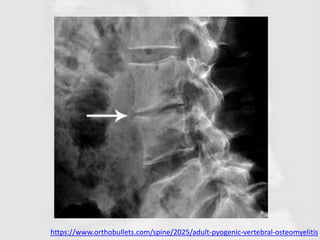

IMAGING

• X-rays

– No change for several weeks;

– Delayed diagnosis, the examination should be repeated.

• Early signs are

– Loss of disc height

– Irregularity of the disc space

– Erosion of the vertebral end-plate

– Reactive new bone formation

– Soft-tissue swelling may be visible

• The early loss of disc height distinguishes vertebral

osteomyelitis from metastatic disease, where the disc

can remain intact despite advanced bony destruction.

https://www.orthobullets.com/spine/2025/adult-pyogenic-vertebral-osteomyelitis